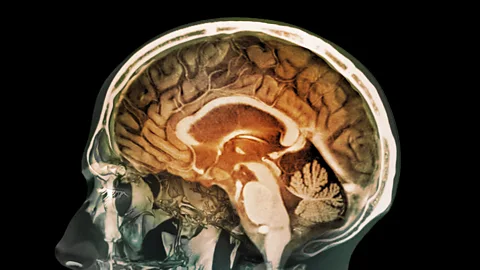

SPLIn the 1970s Godfrey Hounsfield, an engineer with the firm EMI – better known as the home of The Beatles' record label – found a way to see inside the brain with X-rays, better known as a CT scanner. So, in an indirect way, the millions made by The Beatles helped to fund the technology (although some have since argued that the British taxpayer contributed much more).

The Science Museum had one of the world’s first CT scanners. It is enormous, as you can see below: